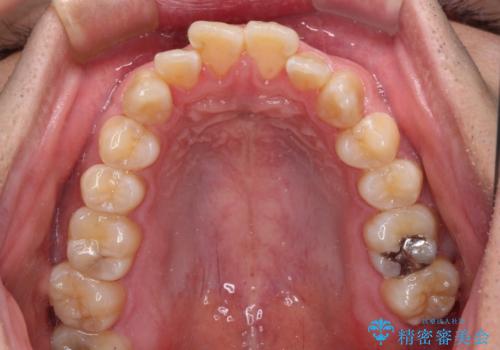

オープンバイトは舌の突出癖により誘発され、治療後も突出癖が残っている容易に後戻りしてしまいます。

治療期間を短縮するためにも、舌突出癖の改善が極めて重要となります。

特にインビザラインではIPRという歯と歯の間を削る処置を多用するため、後戻りによりスペースが生じやすくなるため、治療初期段階での舌のトレーニングが必須となります。